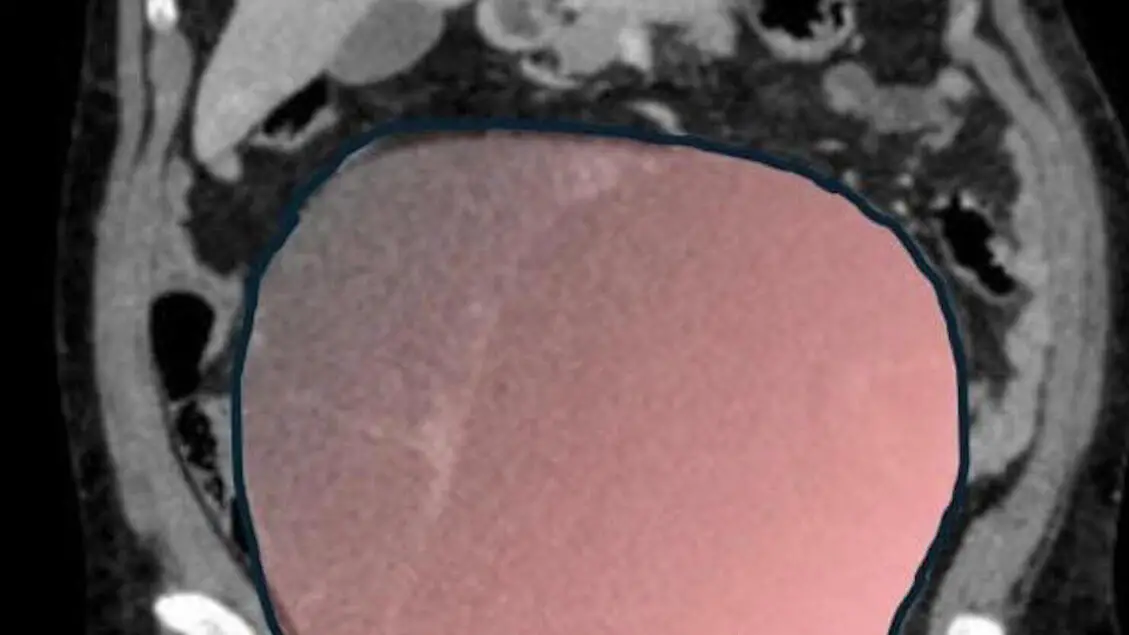

A Torino salvata una donna con tumore ovarico di 6 chilogrammi

Intervento in urgenza al Sant'Anna della Città della salute di Torino